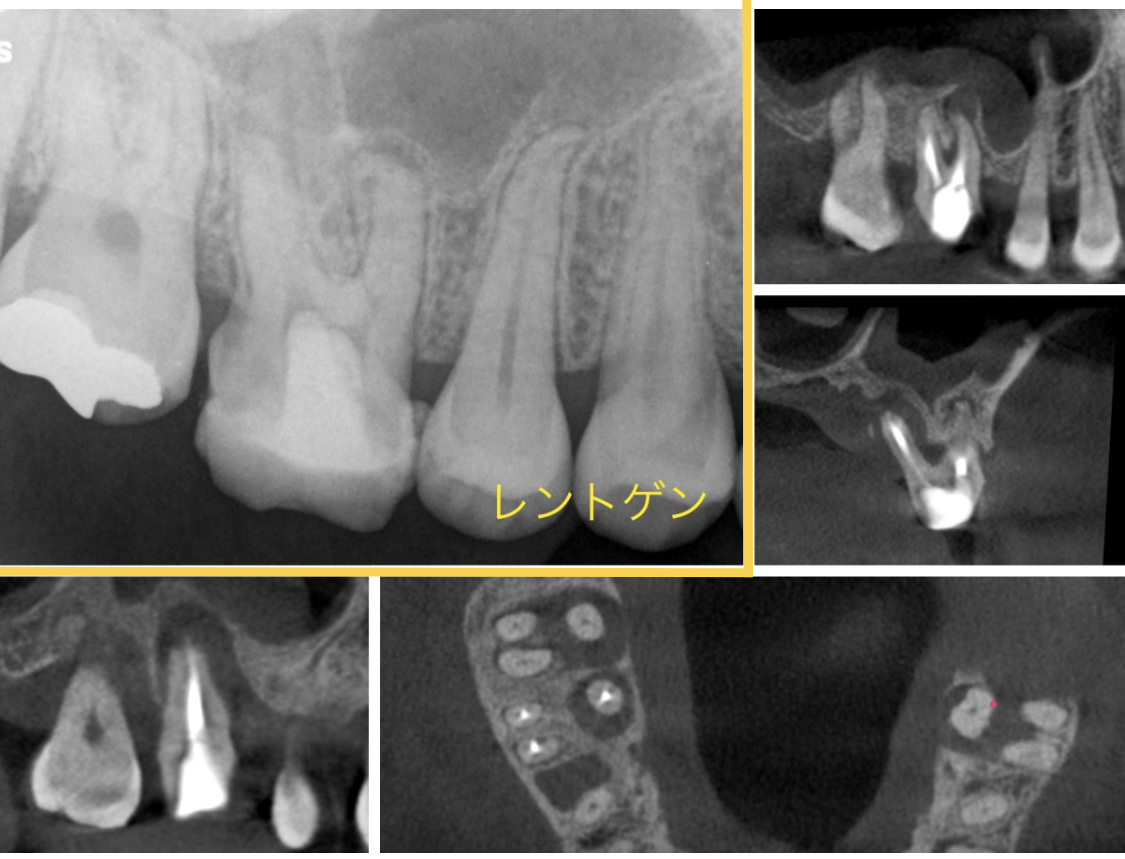

③ CTを使わない診断の限界

通常のレントゲンは2次元画像のため、

・見えない根管

・根の裏側の病変

を正確に把握できないことがあります。

CTを用いることで、原因を立体的に把握でき、診断精度が大きく向上します。